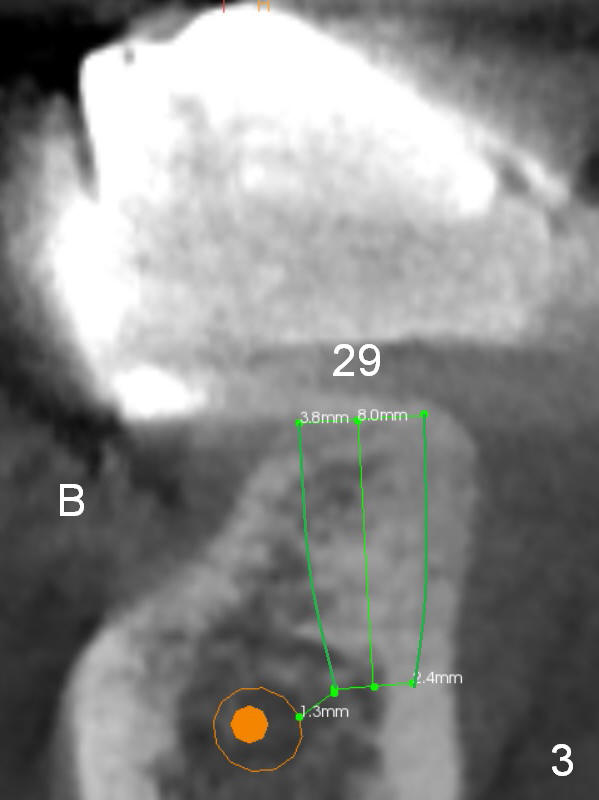

The patient wants to change unstable complete dentures to fixed ones.  Because the problem of pain is associated with the lower left (Fig.1 the left Inferior Alveolar Nerve is more superficial), the lower arch will be reconstructed first.  Totally 6 implants will be placed for bridges/crowns.  Due to time constraint, four implants are placed at the 1st stage (#21, 22, 27 and 28 (Fig.4,5,8,9)); the lower denture will be retained immediately by ball abutments and soft relined.  Two to three months later, two more implants will be placed (at #31 and 20, Fig.2,10).  Note severe atrophy of the crest at #18 and 19 (Fig.11 and 12).  If primary stability is achieved, a fixed immediate provisional will be fabricated.

In contrast to the upper arch, the bone density in the lower arch is high.  The challenge is bone height.  Short implants will be used (6 mm for #31 (Fig.2) and 8 mm for the majority of the others (at premolar and canine sites).  If needed, extra implants will be placed at incisor sites (Fig.6,7 (implant can be longer)) and at #29 (Fig.3) .  If a site is too small for a 3.8 mm 2-piece implant, a 1-piece one may be placed.